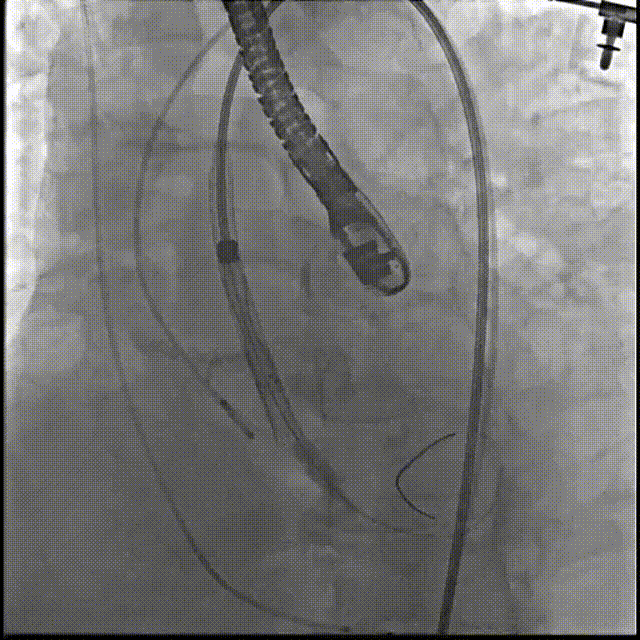

6.根据术前评估及球囊预扩情况,选择23mm沛嘉TaurusElite瓣膜进行植入,在150次/分保护起搏下0位释放瓣膜;

7.造影评估示瓣膜植入深度、工作形态良好、微量瓣周漏,遂予以全部释放;